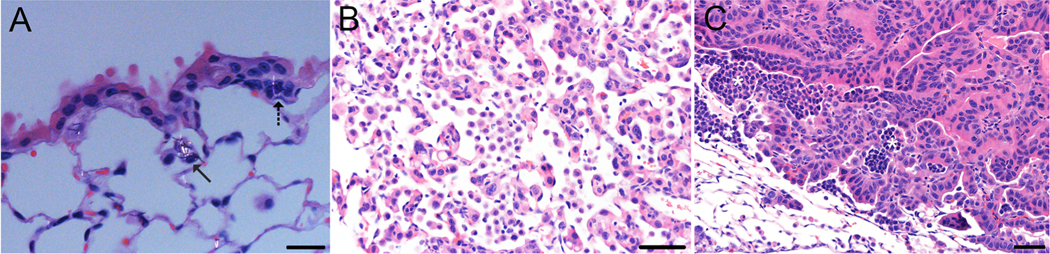

In the lung, carcinogenesis is a multi-stage process that includes initiation by a genotoxic agent, promotion that expands the population of cells with damaged DNA to form a tumor, and progression from benign to malignant neoplasms. We have previously shown that Mitsui-7, a long and rigid multi-walled carbon nanotube (MWCNT), promotes pulmonary carcinogenesis in a mouse model. To investigate the potential exposure threshold and dose-response for tumor promotion by this MWCNT, 3-methylcholanthrene (MC) initiated (10 μg/g, i.p., once) or vehicle (corn oil) treated B6C3F1 mice were exposed by inhalation to filtered air or MWCNT (5 mg/m|) for 5 h/day for 0, 2, 5, or 10 days and were followed for 17 months post-exposure for evidence of lung tumors. Pulmonary neoplasia incidence in MC-initiated mice significantly increased with each MWCNT exposure duration. Exposure to either MC or MWCNT alone did not affect pulmonary neoplasia incidence compared with vehicle controls. Lung tumor multiplicity in MC-initiated mice also significantly increased with each MWCNT exposure duration. Thus, a significantly higher lung tumor multiplicity was observed after a 10-day MWCNT exposure than following a 2-day exposure. Both bronchioloalveolar adenoma and bronchioloalveolar adenocarcinoma multiplicity in MC-initiated mice were significantly increased following 5- and 10-day MWCNT exposure, while a 2-day MWCNT exposure in MC-initiated mice significantly increased the multiplicity of adenomas but not adenocarcinomas. In this study, even the lowest MWCNT exposure promoted lung tumors in MC-initiated mice. Our findings indicate that exposure to this MWCNT strongly promotes pulmonary carcinogenesis.